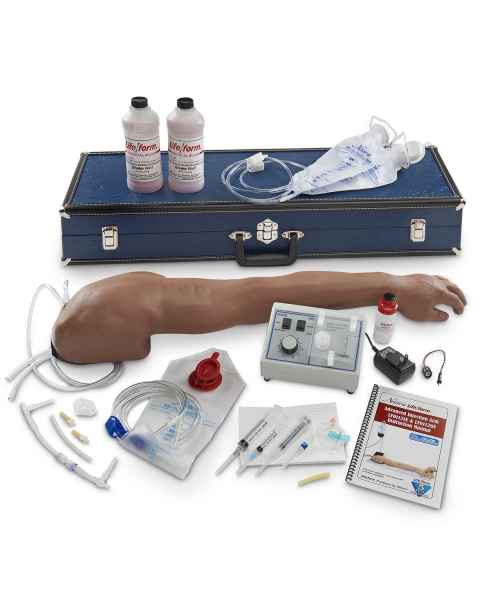

- Medical Training Models

Our Medical Training Models deliver realistic, hands-on training for medical students, nurses, and EMS/EMT professionals. Our product range includes CPR simulators, IV training models, suture trainers, auscultation and catheterization trainers. For lifelike juvenile or adult patient handling, transportation, or extrication training, healthcare educators turn to products such as our Simulaids Rescue Randy Combat Challenge 165-lb. Weighted Adult Manikin. Our Geriatric IV Training Arm is an example of a procedure-focused training tool that includes veins that roll away or disappear as you attempt to catheterize the vessel.